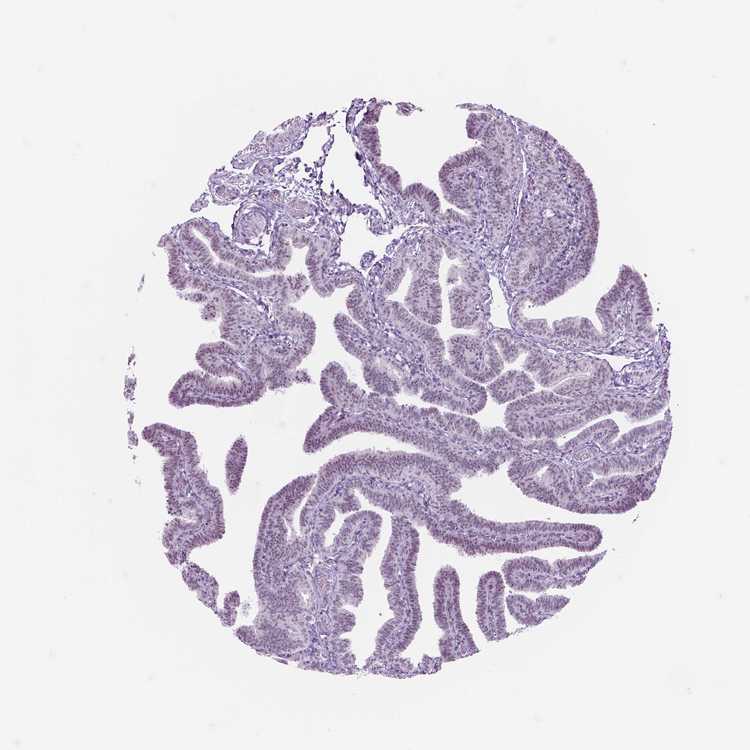

TISSUE PRIMARY DATA FALLOPIAN TUBE Show tissue menu

FALLOPIAN TUBE - Antibody stainingi

Antibody staining in the annotated cell types in the current human tissue is reported as not detected, low, medium, or high, based on conventional immunohistochemistry profiling in selected tissues. This score is based on the combination of the staining intensity and fraction of stained cells.

Each image is clickable and will lead to virtual microscopy that enables deeper exploration of all samples and also displays staining intensity scores, fraction scores and subcellular localization as well as patient and tissue information for each sample.

Antibody HPA029185

Glandular cells Medium